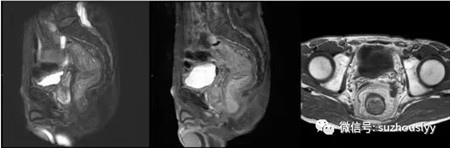

该患者系66岁、男性。因“腹泻1年余,消瘦2月”入院,在当地行肠镜考虑可能是直肠癌,病理结果为(直肠)管状绒毛状腺瘤,来我院消化内科就诊。入院后,胃肠外科、影像科、麻醉科、病理科等多科会诊,经过专家共同讨论后评估该患者可行内镜下治疗,必要时外科干预。术前,充分与患者及家属进行沟通后准备行ESD术,手术全程顺利。术后病理结果示:直肠粘膜绒毛管状腺瘤,腺体伴低级别上皮内瘤变,侧切缘及基底切缘未见病变。目前,患者正在康复中,对诊疗效果极为满意,将于近期出院。

手术病理